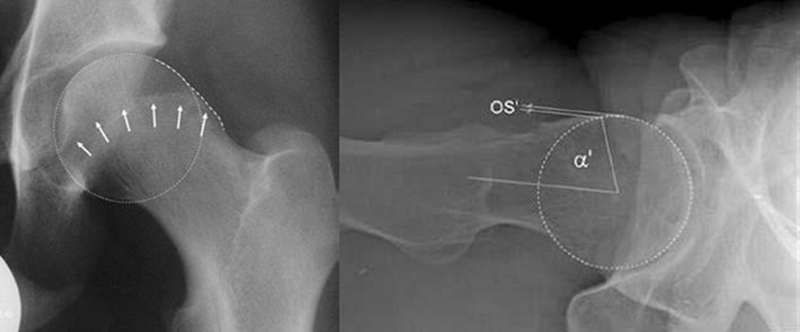

对于髋关节撞击综合征的诊断,不同于髋关节骨性关节炎或者股骨头坏死的患者,不能仅仅通过普通的X光片和双髋关节核磁共振就能确诊,因为造成髋关节撞击综合征的异常骨性凸起通常位于髋臼或者股骨头颈结合区的前外侧,所以临床上常规的髋关节正侧位片上,这个骨性异常的区域恰恰被遮挡了起来,在X光片上成了重叠的影像。在诊断髋关节撞击综合征,会采用一些特殊的影像拍摄方法。对于X光的选择,推荐进行骨盆正位相联合蛙式侧位或Dunn位像。对于盂唇损伤的诊断主要依赖于核磁共振检查,由于双髋关节核磁共振放大率以及扫描方向的问题,不足以判断盂唇的状态,一般需要进行单髋关节核磁共振扫描。

图6 摘自Tannast M, Siebenrock KA, Anderson SE. Femoroacetabular impingement: radiographic diagnosis-what the radiologist should know[J]. Am J Roentgenol, 2007,188(6):1540-1552

图7 摘自Stoller DW. Magnteic Resonance Imaging In Orthopaedics And Sports Medicine[M]. 3rd Edition, 2007